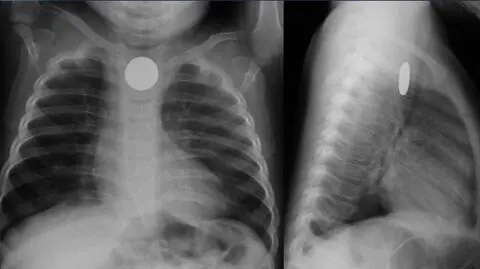

Ciało obce w brzuchu dziecka

Klucze, temperówki, baterie, czyli co próbuje zjeść nasze dziecko. Przykłady nie są wymyślone, przypadki bywają ostre, a finał nie zawsze jest szczęśliwy. Stąd opowieści lekarzy ku przestrodze, czego adresatami są mniej nawet dzieci, a bardziej rodzice.